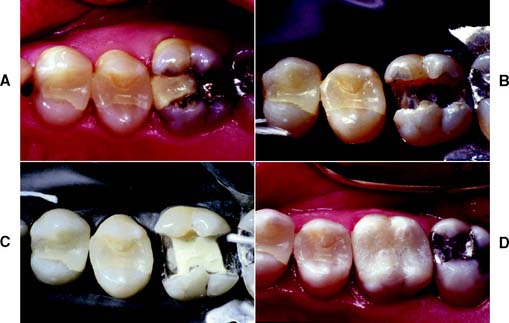

For patients demanding esthetic restorations, ceramic inlays and onlays provide a durable alternative to posterior composite resins. The procedure consists of bonding the ceramic restoration to the prepared tooth with an acid-etch technique. The bonding mechanism relies on acid etching of the enamel and the use of composite resin, as seen in the resin-retained fixed dental prosthesis technique (see Chapter 26). Bonding to porcelain is achieved by etching with hydrofluoric acid and the use of a silane coupling agent (materials are identical to those marketed as porcelain repair kits). A similar restoration entails the use of laboratory-processed composite resin instead of the ceramic.

A ceramic inlay can be used instead of amalgam or a gold inlay for patients with a low caries rate who require a Class II restoration and wish to restore the tooth to its original appearance. It is the most conservative ceramic restoration and enables most of the remaining enamel to be preserved.

Ceramic inlays and onlays can be extremely esthetic restorations. The restoration wear associated with posterior composite restorations is not a problem with the ceramic restorations. Marginal leakage associated with polymerization shrinkage and high thermal coefficient of expansion of the resin is reduced, because the luting layer is very thin.

Accurate occlusion can be difficult to achieve with ceramic inlays and onlays. Because they are fragile, intraoral occlusal adjustment is impractical before they are bonded in place. Therefore, any areas of adjustment need careful finishing and polishing, which is a time-consuming procedure. Rough porcelain is extremely abrasive of the opposing enamel. Castable glass-ceramic restorations (see Chapter 25) are less abrasive than the traditional feldspathic porcelain. Wear of the composite resin-luting agent can be a problem, leading to marginal gaps. These eventually allow chipping or recurrent caries. Accuracy is important with these restorations, because accurately fitting restorations (marginal gaps less than 100 μm) have been shown to reduce this problem significantly. Finishing of the margins can be difficult in the less accessible interproximal areas. Resin flash or overhangs are difficult to detect and can initiate periodontal disease.